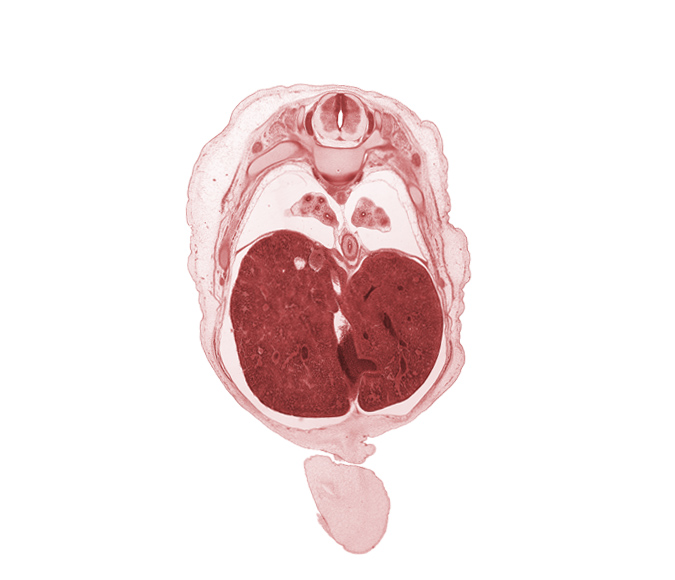

Carnegie Embryo #462 | Location: 4-02-03

Keywords: T-8 intercostal nerve, T-8 spinal ganglion, T-8 spinal nerve, afferent hepatic vein, amnion on surface of umbilical cord, azygos vein, diaphragm, ductus venosus, esophagus endoderm, falciform ligament, inferior vena cava (hepatic part), left lobe of liver, lower lobe of left lung, lower lobe of right lung, pleural cavity, rib 9, right lobe of liver, sympathetic trunk

Source: The Virtual Human Embryo.